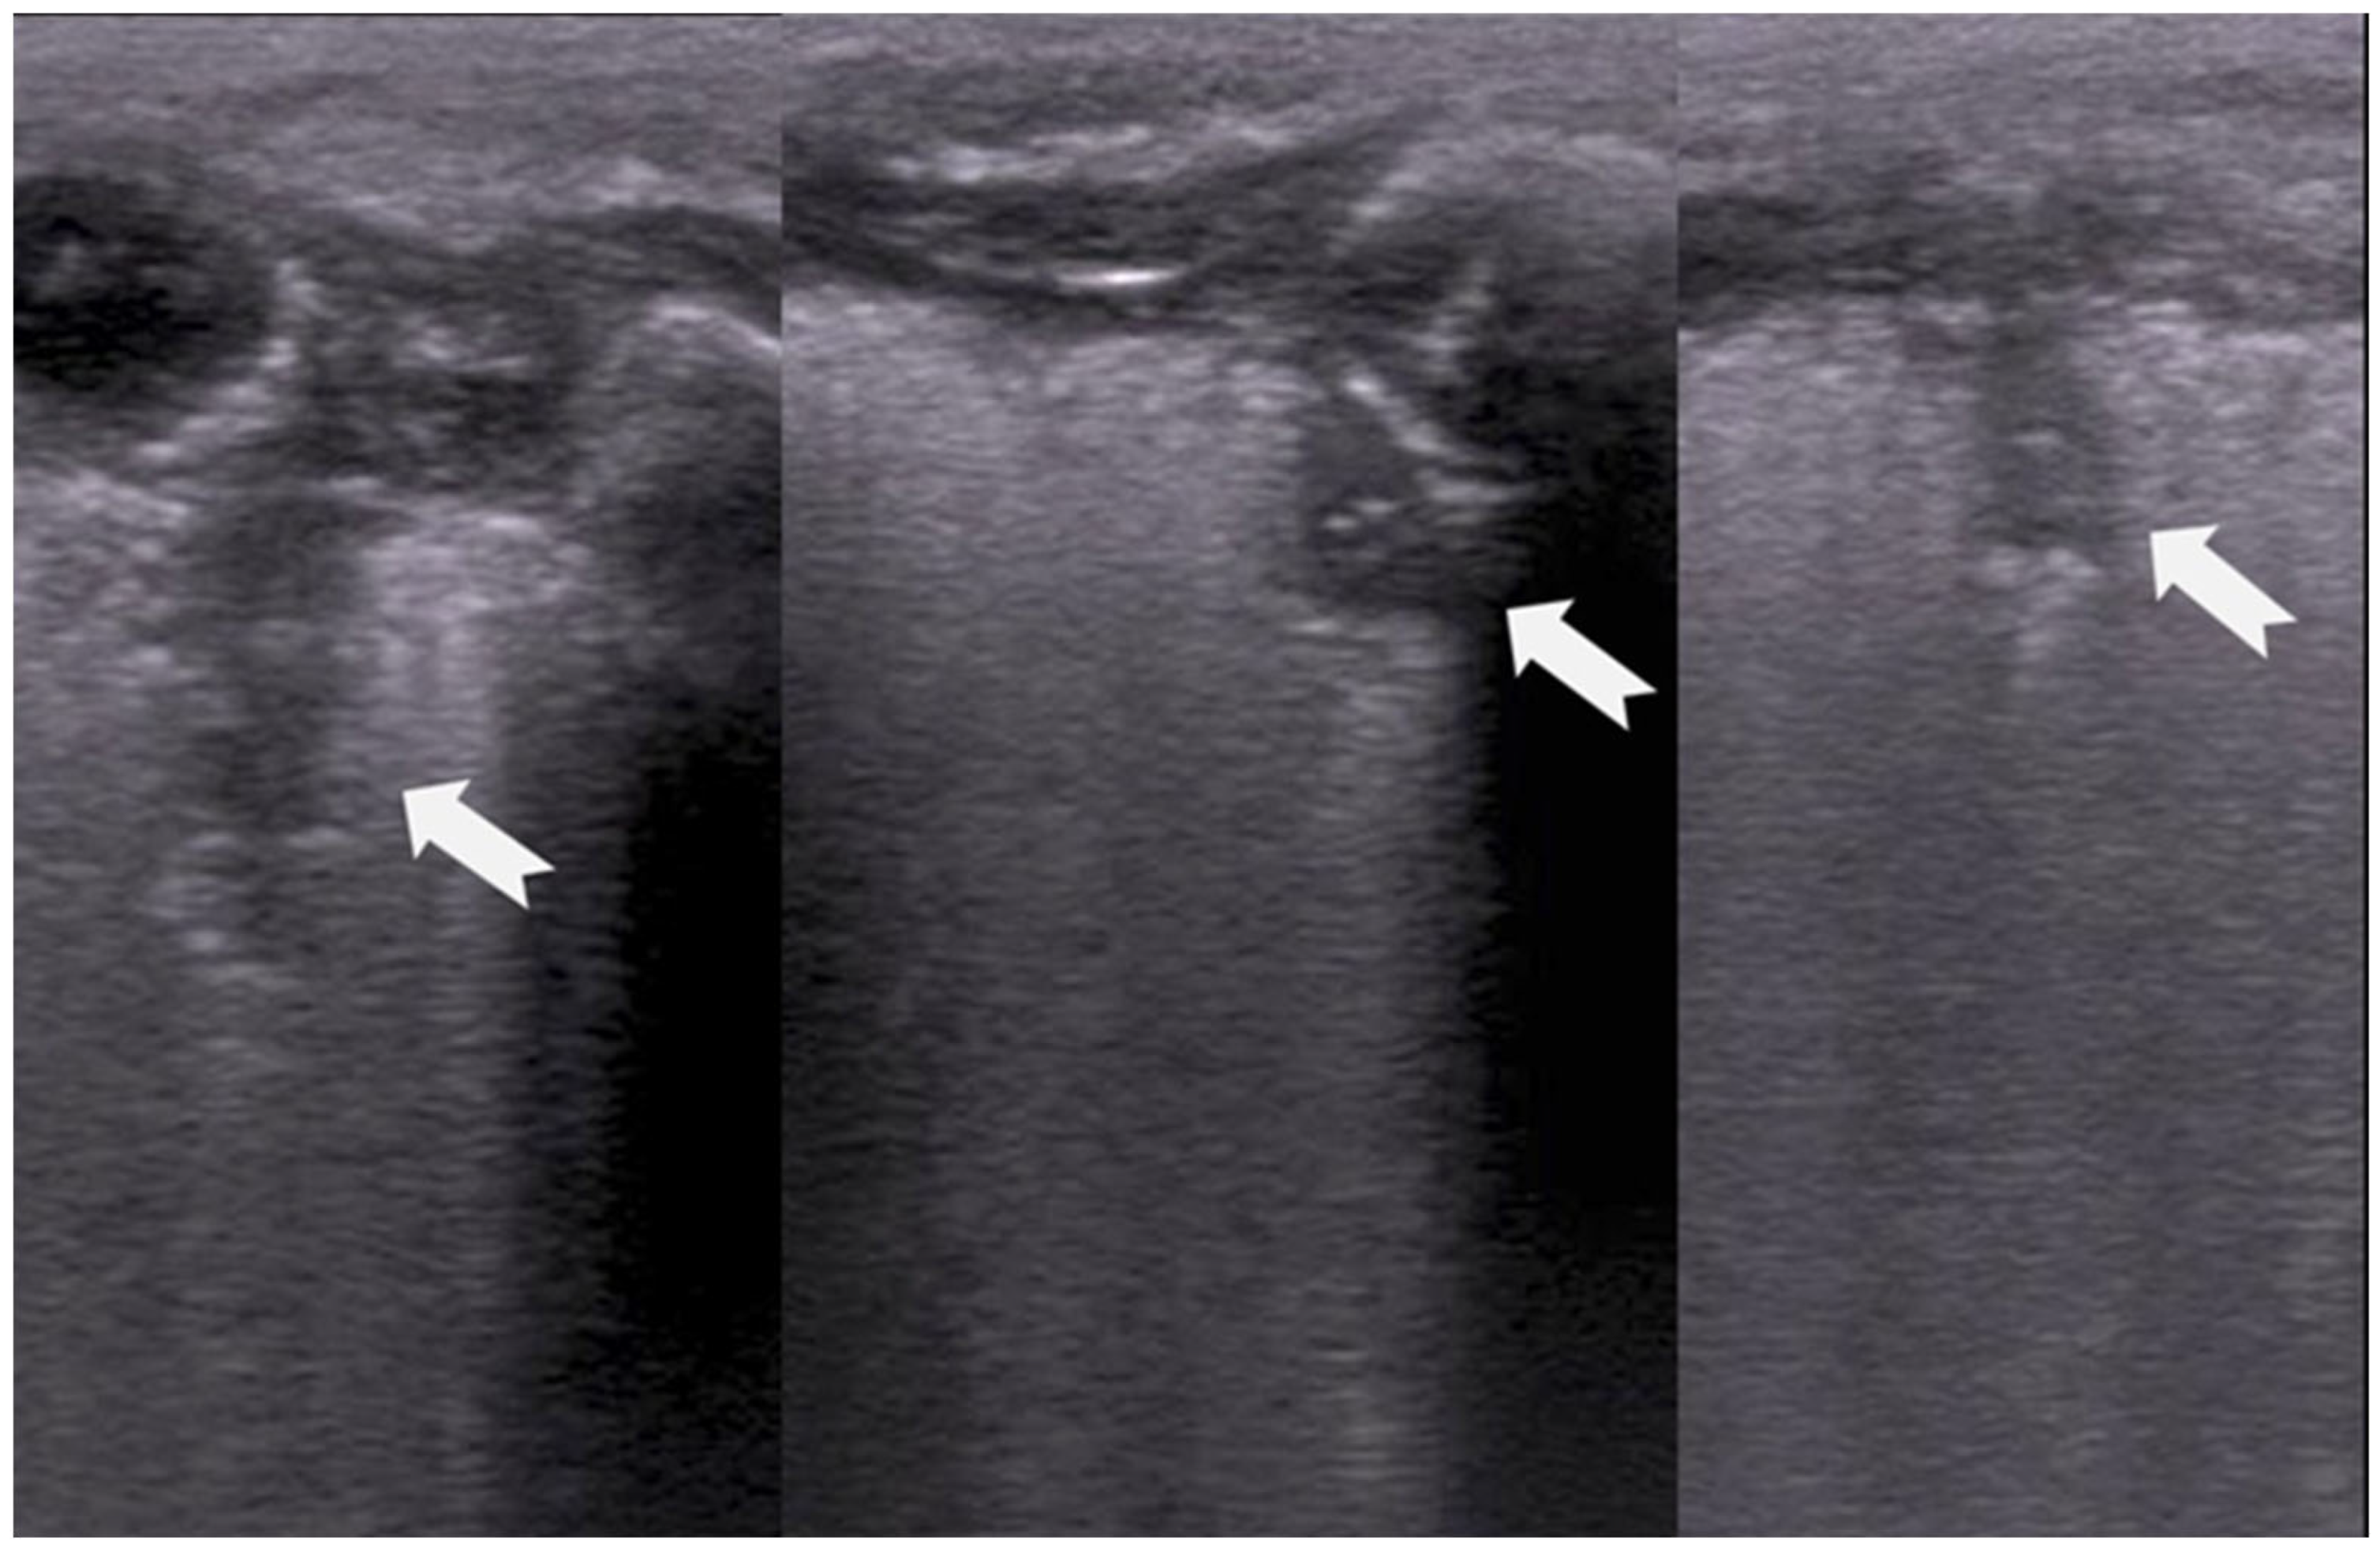

3.1.4. Sliding Lung Sign

The “sliding lung sign” is a key dynamic ultrasound finding that indicates normal lung expansion and pleural integrity. It refers to the respiratory-synchronous movement of the pleural line, which represents the interface between the parietal pleura lining of the chest wall and the visceral pleura covering the lung surface, which appears as a shimmering or “ants on a log” motion in ultrasound images. This shimmering or “ants on a log” motion seen during real-time ultrasound is caused by the relative displacement of the pleural layers during ventilation, as the lung expands and contracts against the inner thoracic cavity (Figure 5) [6,15].

Figure 5.

Sliding lung sign (a real-time image or video is needed to understand the movement).

The presence of the “sliding lung sign” confirms normal pleural apposition and effectively rules out pneumothorax at the site of examination. ‘Sliding lung’ is best visualized in B-mode and confirmed using M (motion)-mode, where it is associated with a characteristic “seashore sign” (see definition below). The presence of these signs further supports normal lung movement, while their absence can suggest pleural separation, as seen in pneumothorax, pleural adhesions, some cases of severe lung consolidation, or even tumors. Clinically, the sliding lung sign serves as a critical marker of pleural contact and is essential for the bedside LUS assessment of neonates, infants, children and adults [15].